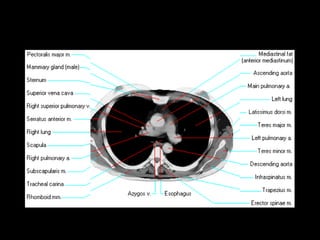

The document discusses the anatomy of the chest x-ray and CT scan by describing the lobes of the lungs and their locations. It also mentions the heart, mediastinum, hilum, and ribs. Several axial, coronal, and sagittal CT images are included with labels pointing out structures like the trachea, bronchi, lobes of the lungs, and fissures. In summary, the document provides an overview of lung and chest anatomy as seen on x-rays and CT scans through text descriptions and labeled medical images.